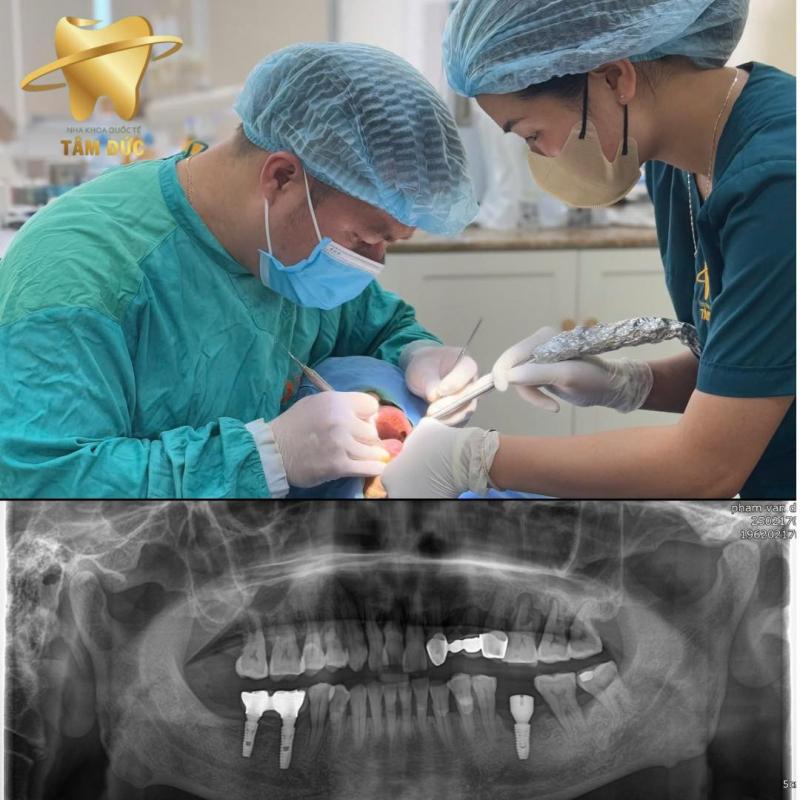

Nha Khoa Quốc Tế Tâm Đức

Gọi điệnKhi nhắc đến địa chỉ chăm sóc răng miệng uy tín tại Đông Anh, Nha Khoa Quốc Tế Tâm Đức luôn là cái tên được nhiều khách hàng tin tưởng lựa chọn. Phòng khám chú trọng trải nghiệm toàn diện – từ thăm khám nhẹ nhàng, tư vấn rõ ràng đến quy trình điều trị hiện đại, giúp mỗi khách hàng cảm thấy yên tâm ngay từ lần đầu ghé thăm.

- Cấy ghép Implant chuẩn quốc tế

Ưu điểm nổi bật tại Nha Khoa Quốc Tế Tâm Đức:

- Đội ngũ bác sĩ giàu kinh nghiệm, tận tâm với khách hàng

- Ứng dụng công nghệ hiện đại, quy trình an toàn – chuẩn y khoa